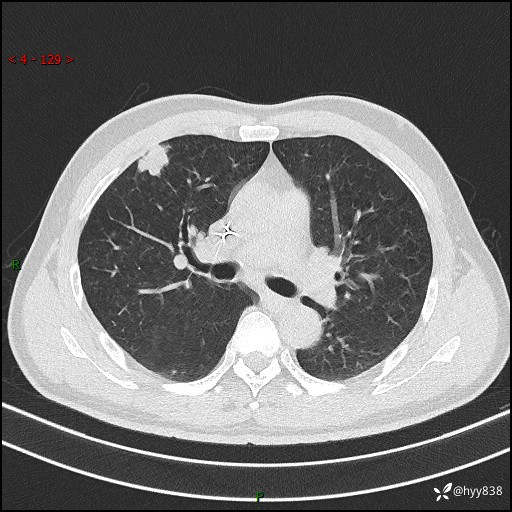

现病史:者10余天前因胸闷就诊于我院心血管内科,行胸部CT提示右肺上叶结节(24mm×16mm),考虑肿瘤性病变可能。无畏寒、发热、盗汗,无咳嗽咳痰,无咯血,无胸痛,无呼吸困难等不适,未予特殊处理。今为求进一步诊治,前来我院就诊,门诊以“肺结节待查”收住入院。 患者自起病来精神、食欲、睡眠尚可,体力下降,体重无明显变化。

胸部CT平扫+增强